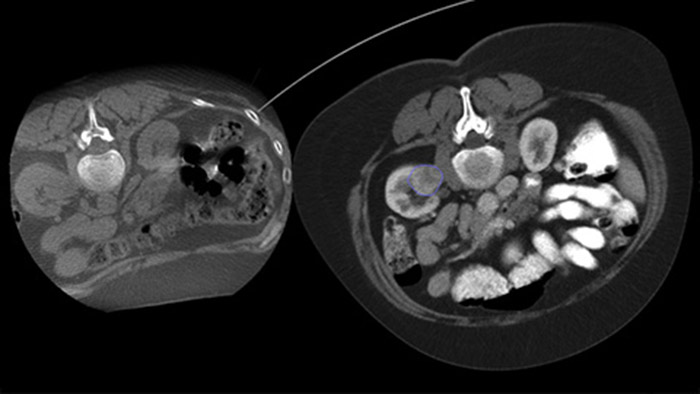

XperGuide Ablation* provides comprehensive assistance for treatment planning and live needle guidance. It offers unique Parallax Correction to plan needle trajectories for off-center lesions.1 To optimise the needle position for effective ablation, this tool displays the virtual needle path to assist in multiple needle planning. It shows needle characteristics such as ablation zone/isotherm to confirm complete tumor coverage prior to ablation.

Percutaneous ablation (radiofrequency, microwave, and cryoablation), is a well-established minimally invasive treatment of kidney, liver, lung and bone tumors. It is critical to define the tumor boundaries and decide on an optimal number of needles and corresponding needle trajectory to be able to perform a complete tumor treatment and not to cause damage to surrounding tissue. Navigating accurately at low dose to the lesion of interest without needle repositioning increases the opportunity for success and reduces risk for complications of your biopsies or ablations. Confirmation of ablation treatment endpoint can be accomplished with 3D imaging while the patient is still on the table.

Dual View allows the overlay of a pre-procedure 3D image (CT/MR/PET-CT) on an intra-procedure 3D CBCT Dual to better visualisation the lesions and access critical input for needle planning.

XperGuide provides highly accurate live image guidance of each needle to a targeted position by overlaying pre-planned trajectories with fluoroscopic imaging.3

With CBCT acquire a post-ablation CBCT to demonstrate the extent of tumor coverage and confirm completeness of your treatment.